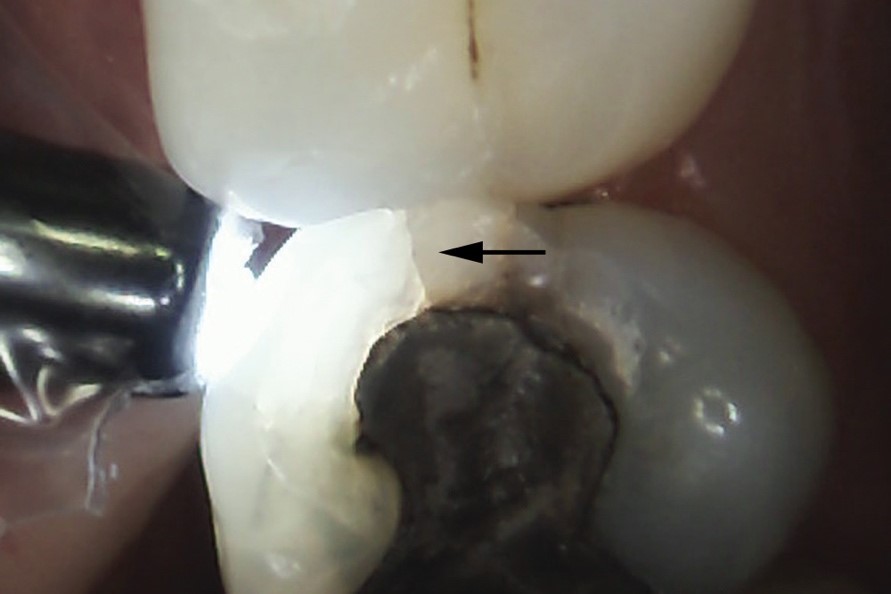

Tổn thương nứt vỡ răng có tiến triển tới ngà, đặc trưng là sự truyền sáng bị đứt gãy tại đường nứt, khiến bên chiếu sáng hấp thụ hết lượng ánh sáng đơn sắc, trong khi nửa còn lại bên đường gãy lại tối màu hơn |